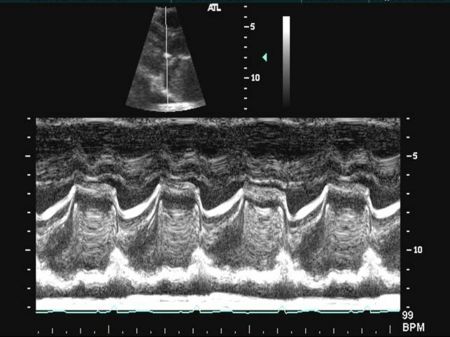

M Mode in Mitral Valve Prolapse

- Systolic bowing of the posterior mitral valve leaflet

M Mode in Mitral Stenosis

- Leaflet tips bright (calcified) and thickened

- E/F slope decreased